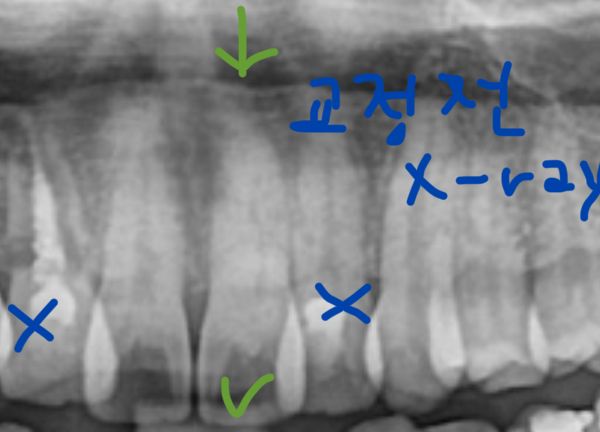

치아사진과 파노라마(교정 전 것이지만 상태는 현재와 동일) 보시고, 검은색으로 비치는 게 뭔지 알려주시면 감사하겠습니다!! 확실하지 않아도 되니 의심되는 것 전부 말씀해주시면 감사하겠습니다..!ㅜㅜ

방사선 사진 상 해당 치아에 외부충격의 외상이든, 앞니로 딱딱하거나 질긴 것을 세게 물었든 힘이 가해져서 치수강 위축이 생긴 상태입니다 이로보아 변색은 신경과 관련된 것이 높을 것으로 판단은 됩니다

교정전 고르지 않은 두번째 앞니 배열때문에 해당 부위로 음식물이 잘 껴서 충치가 있었을 확률도 높습니다

현재 방사선 사진도 한번 찍어보면 해당 부위 내부에 충치가 있는지 확인 해볼 수 있을 것입니다